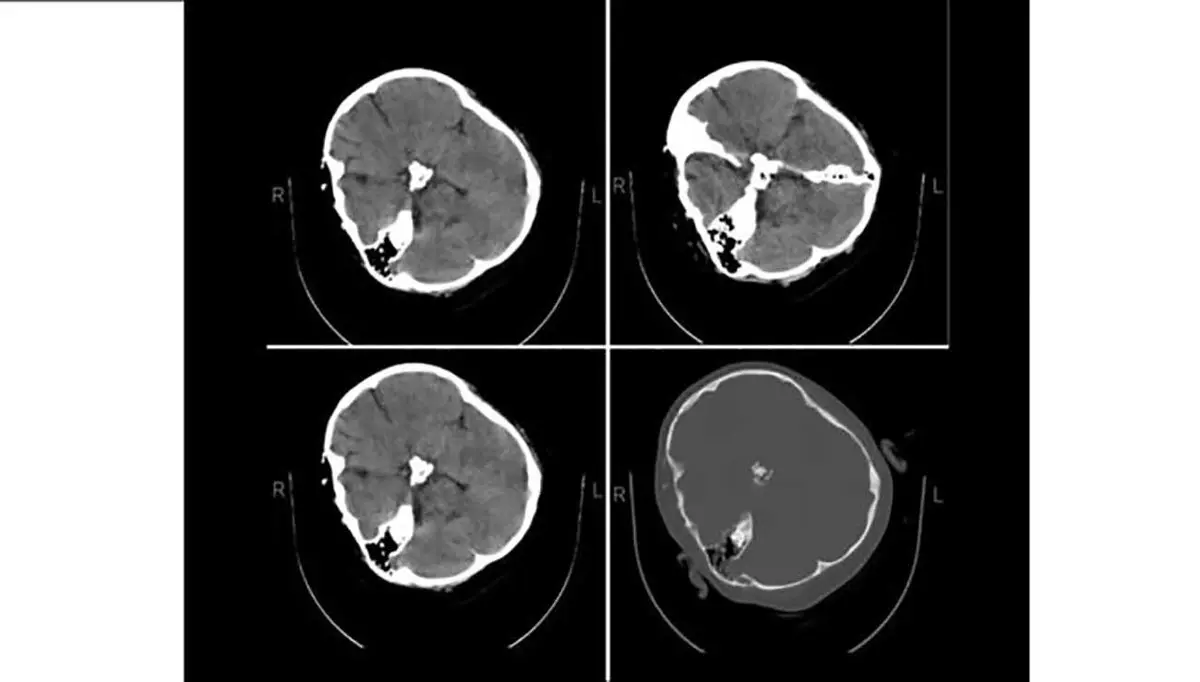

در بیانیه متخصصین نرورادیولژی هیأت بورد رادیولوژی وزارت بهداشت که در پاسخ به استعلام ریاست نظام پزشکی صادر شده، آمده است: «با توجه به استعلام ریاست نظام پزشکی، متخصصین نرورادیولژی هیات بورد رادیولوژی وزارت بهدشت، پس از بررسی تصاویر سیتی اسکن مغز مرحومه مهسا امینی اعلام میدارد در سیتی اسکن که بهصورت فیلمبرداری از، مانیتور تهیه شده است، خونریزی در پارانشیم مغزی، خونریزی اپیدورال و سابدورال دیده نمیشود.»